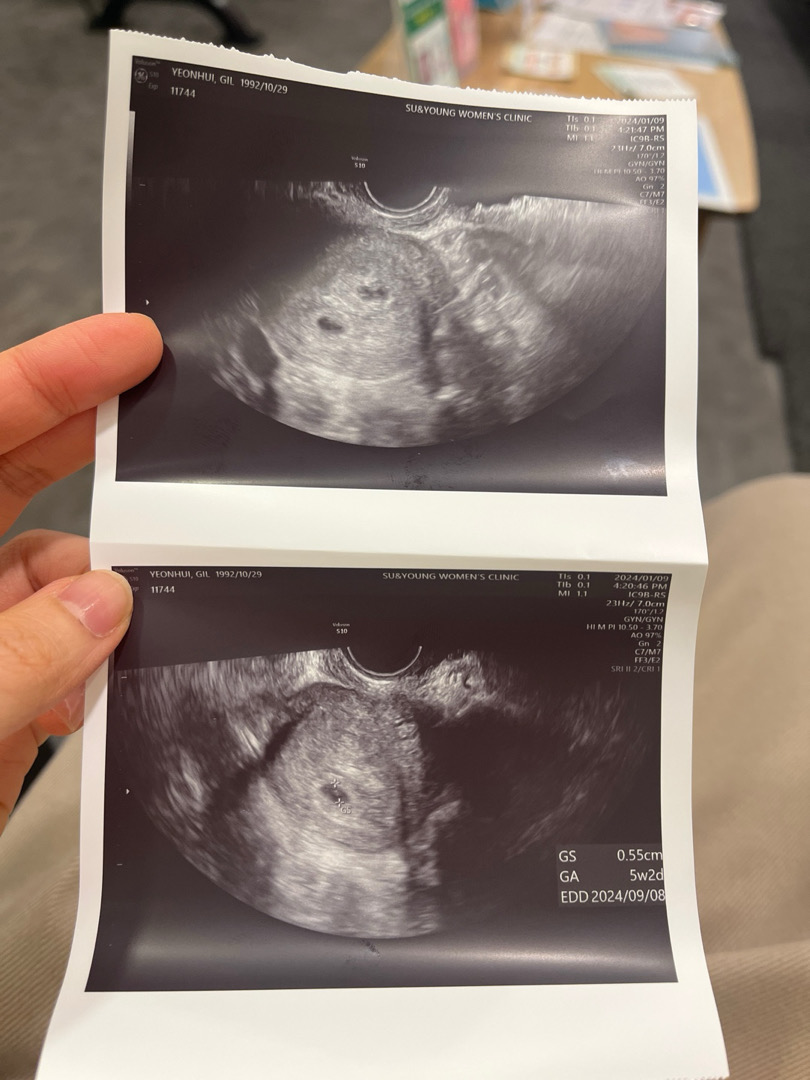

쌍둥이일까요??

안녕하세요! 지난주에는 아기집이 안보여서 걱정이였는데 오늘 가보니 아기집이 잘 보였어요!! 그런데 아기집이2개라고 쌍둥이 같다고해요!! 정확한건 담주에 알 수있다구 남편에게만 말하라고 하네요ㅎㅎㅎ 사진은 아기집 2개사진과 1개사진을 주셨어요! 사진상 쌍둥일까요?? 제가 쌍둥이 소리에 난황을 못 여쩌봤는데 난황이 있을까요??